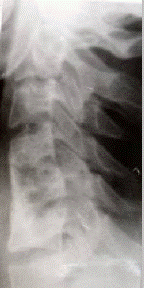

В качестве иллюстрации приводим рентгенологическую картину формирования костного блока у больного В., 21 лет, которому выполнен спондилодез на двух уровнях по поводу нестабильного перелома С6

позвонка (см. рисунок 1).

а) б) в)

Рис.1. Больной В., 21 лет. Д–з: нестабильный перелом тела С6

позвонка.

а – при поступлении; б – 7 дней после операции; в – 11 недель после операции.